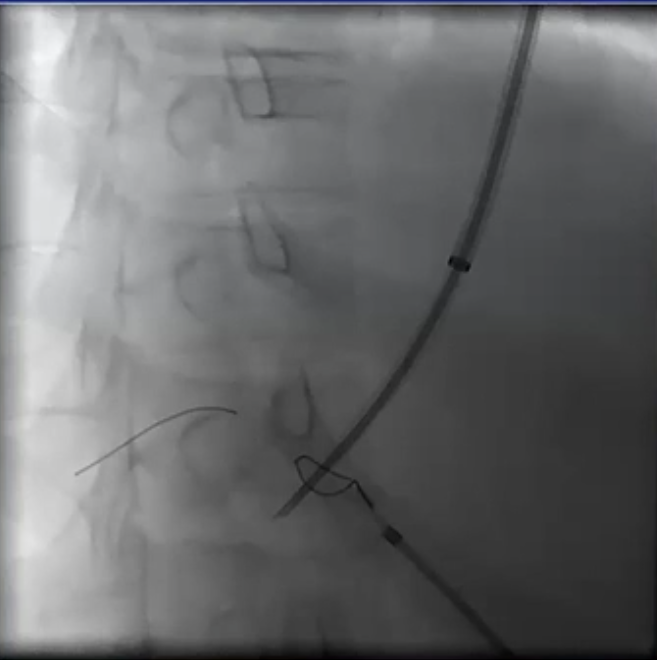

从技术层面来讲,要准确击中“PV 锁定点”并非易事,这个点的位置比预期的要靠后,需要使用斜位来瞄准发力。

急性门静脉血栓(续) 对于那些成功实施经颈静脉经肝到达门静脉内急性血栓内,并进行了溶栓和抗凝治疗的患者,是否应该进行经颈静脉肝内门体分流术(TIPS)呢(放支架)? 这一问题存在争议。 。一个过于激进的TIPS手术,导致门静脉分支没有血流,从而发展成肝硬化 妥协的操作是设置一个“小TIPS”,即放置一个直径较细(直径5毫米左右)的TIPS裸支架,溶栓导管经支架通过,进行抗凝和溶栓治疗后,同时保留 TJ 对 SMV/PV 的访问权限,以防再次发生血栓情况。 一例术后急性门静脉血栓病例,最终影像显示门静脉根部血流情况良好,这还不够理想,担心会再次发生血栓,且门静脉压(PSG)超过 12 毫米汞柱,因此增加了经导管动脉溶栓术(TIPS)的治疗方案。